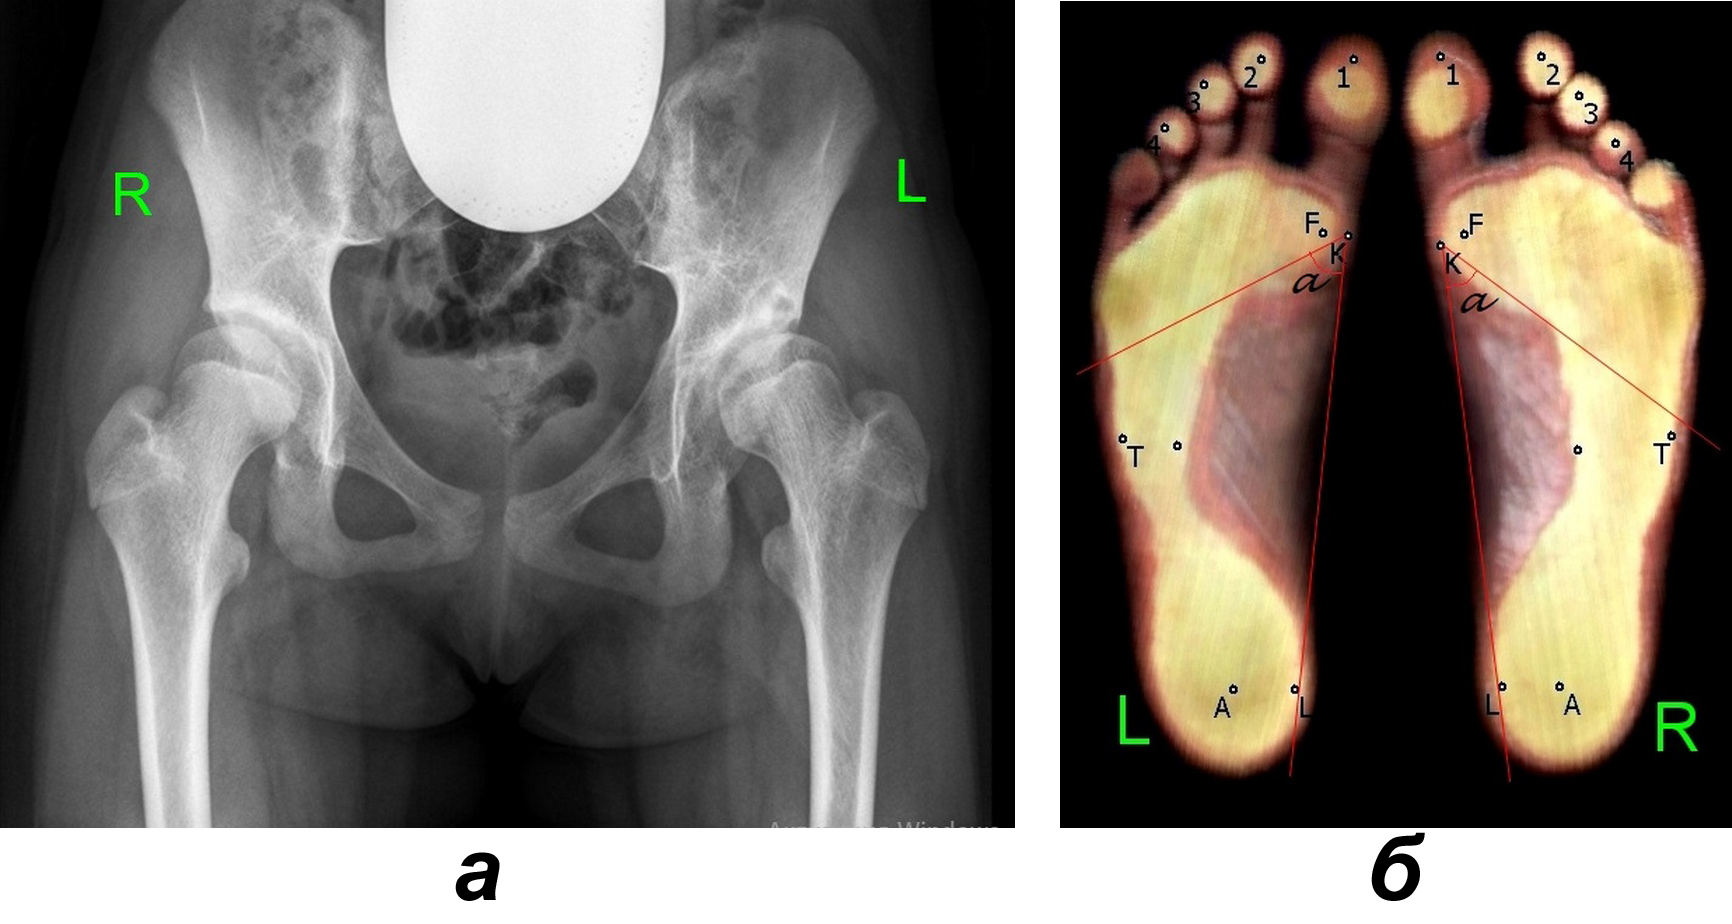

Проведено биомеханическое обследование 23 детей в возрасте от 13 до 17 лет с односторонним ДПБ Crowe I группы (рис. 1, а). Из них у 10 пациентов был левосторонний ДПБ, у 13 – правосторонний. Контрольную группу составили 18 здоровых детей аналогичного возраста.

Рис. 1. Пациентка П., 16 лет, с дисплазией Crowe I группы: а – рентгенограмма тазобедренных суставов (выявляется подвывих бедра слева); б – плантограмма стоп интактной и поражённой сторон (выявляется увеличение угла Кларка α слева, снижение опорности головки 1-й плюсневой кости обеих стоп, больше слева)

Показатели плантографических характеристик здоровых детей и пациентов с односторонним ДПБ представлены в табл. 1. Наибольшее количество отклонений от нормы по сравнению со здоровыми детьми выявлено у больных при двуопорной нагрузке на стопы: отмечается значимое снижение показателей всех индексов опоры t, m и s – не только на стопе поражённой конечности, но и на интактной стороне. При этом на стороне поражения индекс m был значительно снижен по сравнению с интактной стороной, что указывает на выраженное снижение опорности головки 1-й плюсневой кости стопы поражённой нижней конечности. Кроме того, на стопах поражённой стороны патологически увеличены углы Кларка a (см. рис. 1, б), что свидетельствует о повышении высоты их продольных сводов [11], которое приводит к снижению общей площади опоры стоп. При одноопорной нагрузке на стопы все плантографические индексы у больных значимо снижены с обеих сторон по сравнению с нормой, что указывает на ухудшение рессорной функции поперечного и продольных сводов стоп поражённой и интактной конечностей, что может быть обусловлено тенденцией к ригидности сводов.